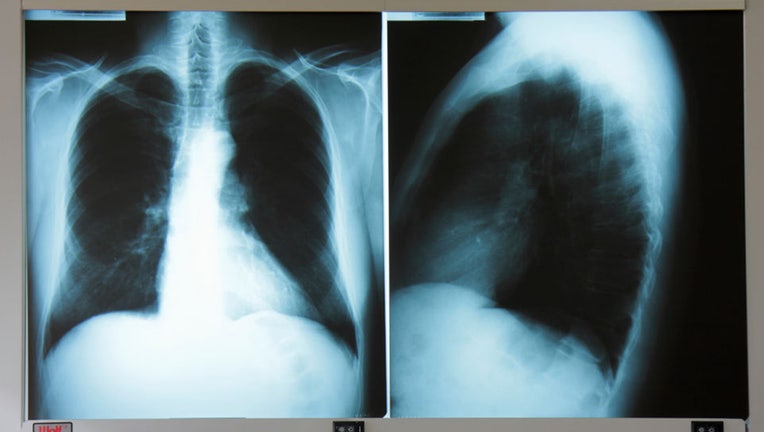

FILE - An adult male chest x-ray.

Valley fever (also called coccidioidomycosis or "cocci") is a significant cause of pneumonia, said Dr. Brad Perkins, chief medical officer at Karius, a company that provides advanced diagnostics for infectious diseases.

"This is a fungus," said Perkins, a former Centers for Disease Control and Prevention official who led the anthrax bioterrorism investigation. "Most causes of pneumonia are caused by bacteria. This is a fungus that lives in the soil and is breathed in dusty situations, whether it's a dust storm or around construction or excavation."

Valley fever and COVID-19 share many of the same symptoms as a cough, difficulty breathing, fever, tiredness or fatigue. In rare cases, it can spread to other body parts and cause severe disease.